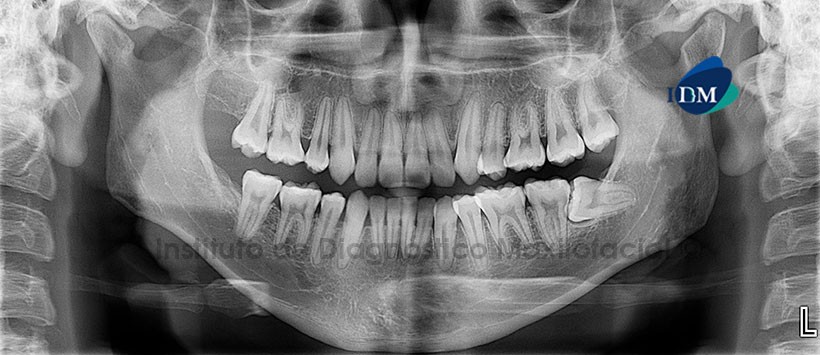

A la evaluación de la radiografía panorámica se aprecia aplanamiento de los contornos de los cóndilos mandibulares, primeras premolares ausentes, obliteración de la cámara pulpar de las piezas 13 y 33, obliteración de la cámara y conducto radicular a nivel de la pieza 43; pieza 3.8 impactada en posición horizontal (Figura 1).